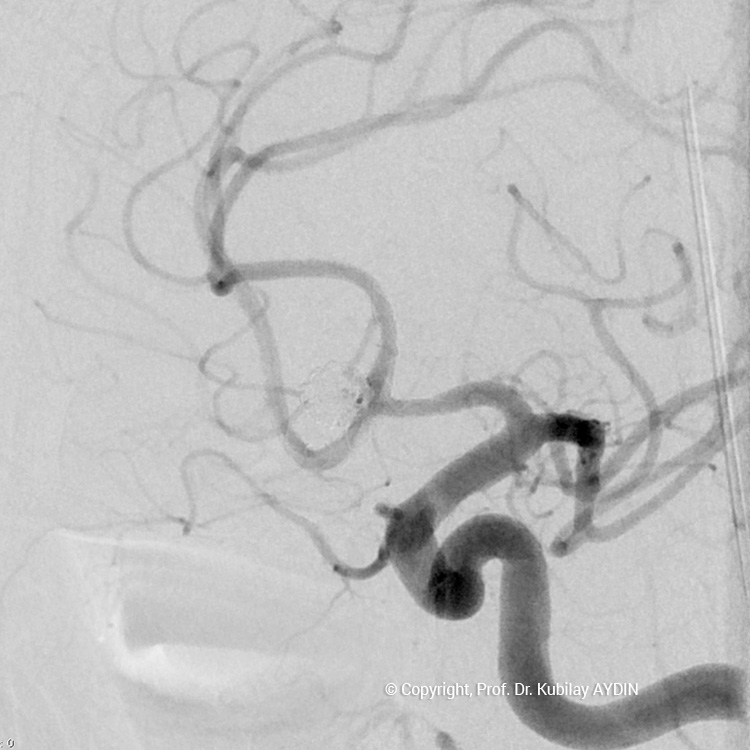

Tüm kapalı anevrizma tedavileri, hasta genel anestezi ile uyutularak gerçekleştirilir. Kapalı anevrizma tedavisinin tüm aşamaları, bacak atardamarı içine yerleştirilen 2 mm çaplı (kurşun kalemden daha ince) bir özel kateter yoluyla uygulanır. Bu küçük giriş noktasından damar içine çok ince (0.5mm çapında) ve yumuşak yapıda mikrokateter adını verdiğimiz özel plastik tüp gönderilir. Anevrizmayı kapatmak için kullandığımız bu mikrokateter, anjiografi cihazında izlenerek anevrizmanın bulunduğu damar içine yönlendirilir. İçi boş, çok ince ve yumuşak bir plastik tüp şeklinde olan mikrokateterin ucu, anevrizma kesesi içine yerleştirilir. Daha sonra bu mikrokateter içerisinden gönderilen platinden yapılmış çok yumuşak “koil” adı verilen tellerle anevrizma kesesi doldurulur. Koiller, anevrizma kesesi içinde bir yumak oluşturup, anevrizma içine kan girişini engeller. Anevrizma kesesi, koillerle tamamen doldurulup, anevrizma içine kan girişi tam olarak durduğu zaman, mikrokateter anevrizma içinden geri alınarak işlem tamamlanır. Anevrizmanın koil adı verilen özel tellerle doldurularak kapatılma işlemine, "koilleme" adı verilir. Anevrizmanın koillenerek kapatılması işlemi, oldukça güvenli ve etkili bir tedavi yöntemidir. Kanamamış beyin anevrizması olan hasta, koilleme yöntemi ile tedavi edildikten 1-2 gün sonra hasta normal günlük yaşamına dönebilir.